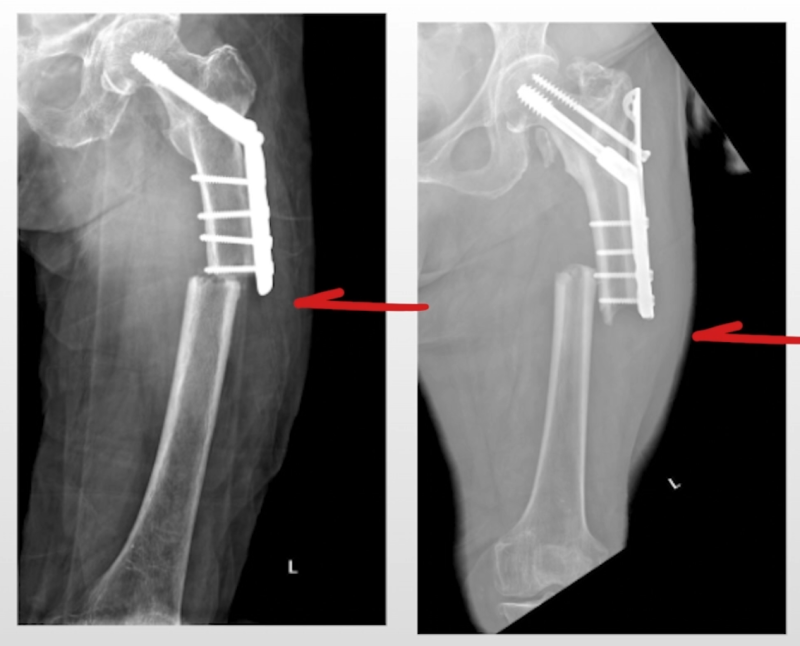

이 이미지에서는 수술 후 고정장치가 뼈에 어떻게 위치해 있는지를 보여줍니다.